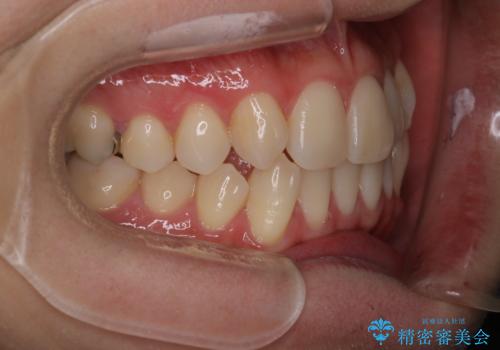

右上2番が欠損しているため、見た目と噛み合わせの両方のバランスを整えるために経過を追いながら必要な部位にゴム掛けをしました。

最終的に、見た目も噛み合わせも患者様に満足いただけました。

また矯正後、患者様の希望で

メタルインレーをセラミックインレーにやりかえさせていただき、さらに綺麗に仕上がりました。